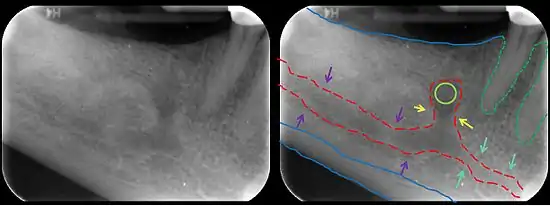

In human anatomy, the mandibular canal is a canal within the mandible that contains the inferior alveolar nerve, inferior alveolar artery, and inferior alveolar vein. It runs obliquely downward and forward in the ramus, and then horizontally forward in the body, where it is placed under the alveoli and communicates with them by small openings.

The mandibular canal is continuous with tow foramina: the mental foramen which opens in the mental region of the mandible and carried the distal fibres of the inferior alveolar nerve as the mental nerve; and the mandibular foramen on medial aspect of ramus, into which the mandibular nerve enters to become the inferior alveolar nerve. The mandibular canal often runs close to the apices of the third molar tooth, and the inferior alveolar nerve can become damaged during removal of this tooth, causing sensory disturbance in the distribution of the nerve. This is sometimes the case for the second or first molar teeth, and care must be taken during removal or root canal treatment in such cases to prevent nerve injury or extrusion of root canal filling materials.[2]

Several variations of the mandibular canal exist with varying frequency. The most common variant is the retromolar canal (~10 % of canals), whereby a branch is given off in the mandibular ramus which terminates in the retromolar region of the mandible. The retromolar canal may cause bleeding during surgery in the retromolar region such as removal of mandibular third molar teeth. Other variants include a bifid canal with a branch: following the course of the main mandibular canal before re-joining it (forward or buccolingual type); terminating at the apex of a tooth, usually the molar teeth (dental type); opening as an accessory mental foramen.[3] A trifid mandibular canal variation has also been described.[4][5]